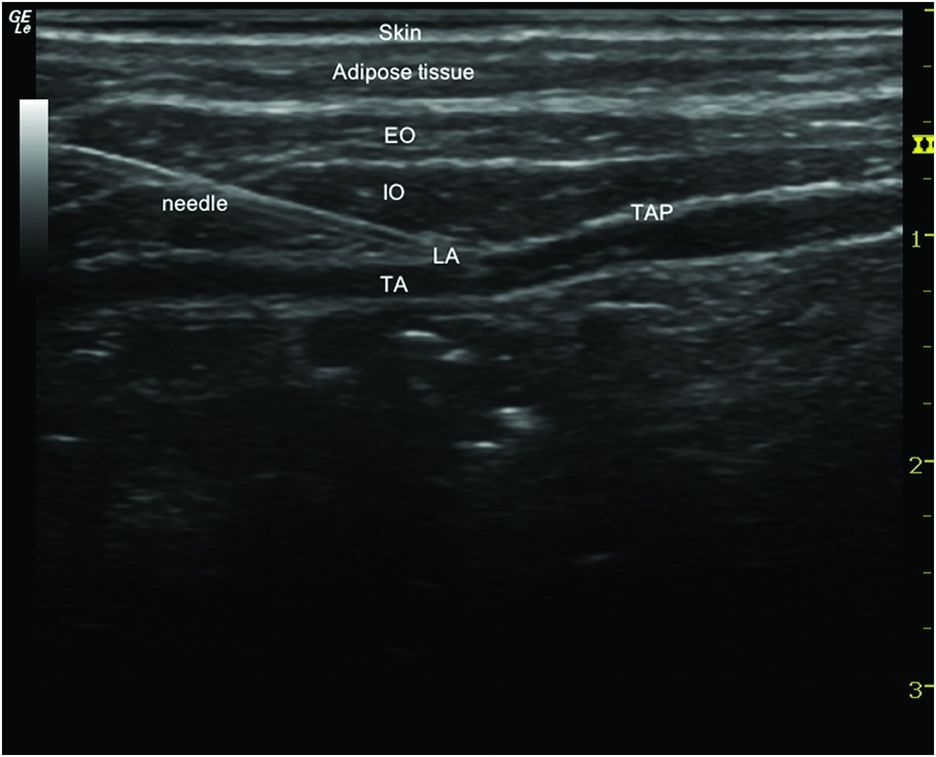

Tap Block Local Anesthetic Dose . The transversus abdominis plane (tap) block is used to produce a dermatomal sensory block of the lower thoracic and upper lumbar afferents. I read with interest the letter by. Multiple small abdominal wall nerves are the primary target for the tap block. Safe dose of local anaesthetic for transversus abdominis plane block. A tap block basically involves deposition of local anesthetic in the plane. Installation of local anesthetics in this plane. These blocks are typically ultrasound (us) guided and involve injecting a local. The transversus abdominis plane (tap) block is a fascial plane block performed by injecting local anesthetic in the plane between. The tap block is a regional technique with significant clinical utility as.

Tap Block Local Anesthetic Dose A tap block basically involves deposition of local anesthetic in the plane. I read with interest the letter by. The transversus abdominis plane (tap) block is used to produce a dermatomal sensory block of the lower thoracic and upper lumbar afferents. Safe dose of local anaesthetic for transversus abdominis plane block. The transversus abdominis plane (tap) block is a fascial plane block performed by injecting local anesthetic in the plane between. A tap block basically involves deposition of local anesthetic in the plane. Multiple small abdominal wall nerves are the primary target for the tap block. The tap block is a regional technique with significant clinical utility as. Installation of local anesthetics in this plane. These blocks are typically ultrasound (us) guided and involve injecting a local.

Active Comparator Transversus abdominis plane (TAP) block performed in operating room for Local Tap Block Local Anesthetic Dose Installation of local anesthetics in this plane. The transversus abdominis plane (tap) block is used to produce a dermatomal sensory block of the lower thoracic and upper lumbar afferents. The transversus abdominis plane (tap) block is a fascial plane block performed by injecting local anesthetic in the plane between. These blocks are typically ultrasound (us) guided and involve injecting a. Tap Block Local Anesthetic Dose.

TAP Block — CRNA Conferences Twin Oaks Anesthesia Tap Block Local Anesthetic Dose The transversus abdominis plane (tap) block is used to produce a dermatomal sensory block of the lower thoracic and upper lumbar afferents. These blocks are typically ultrasound (us) guided and involve injecting a local. Installation of local anesthetics in this plane. A tap block basically involves deposition of local anesthetic in the plane. Multiple small abdominal wall nerves are the. Tap Block Local Anesthetic Dose.

Ultrasoundguided transversus abdominis plane block Anesthesia Key Tap Block Local Anesthetic Dose A tap block basically involves deposition of local anesthetic in the plane. The tap block is a regional technique with significant clinical utility as. I read with interest the letter by. Installation of local anesthetics in this plane. The transversus abdominis plane (tap) block is used to produce a dermatomal sensory block of the lower thoracic and upper lumbar afferents.. Tap Block Local Anesthetic Dose.